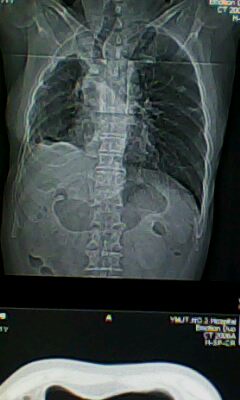

标题: CT25675:男 71 肺癌部分切除术后 3年 [打印本页]

标题: CT25675:男 71 肺癌部分切除术后 3年

1)两肺感染性病变。2)右侧胸膜增厚。3)冠状动脉及主动脉钙化。

1.右肺符合肿瘤切除术后ct表现。

术后改变,双肺内纤维索条影考虑与放疗有关。